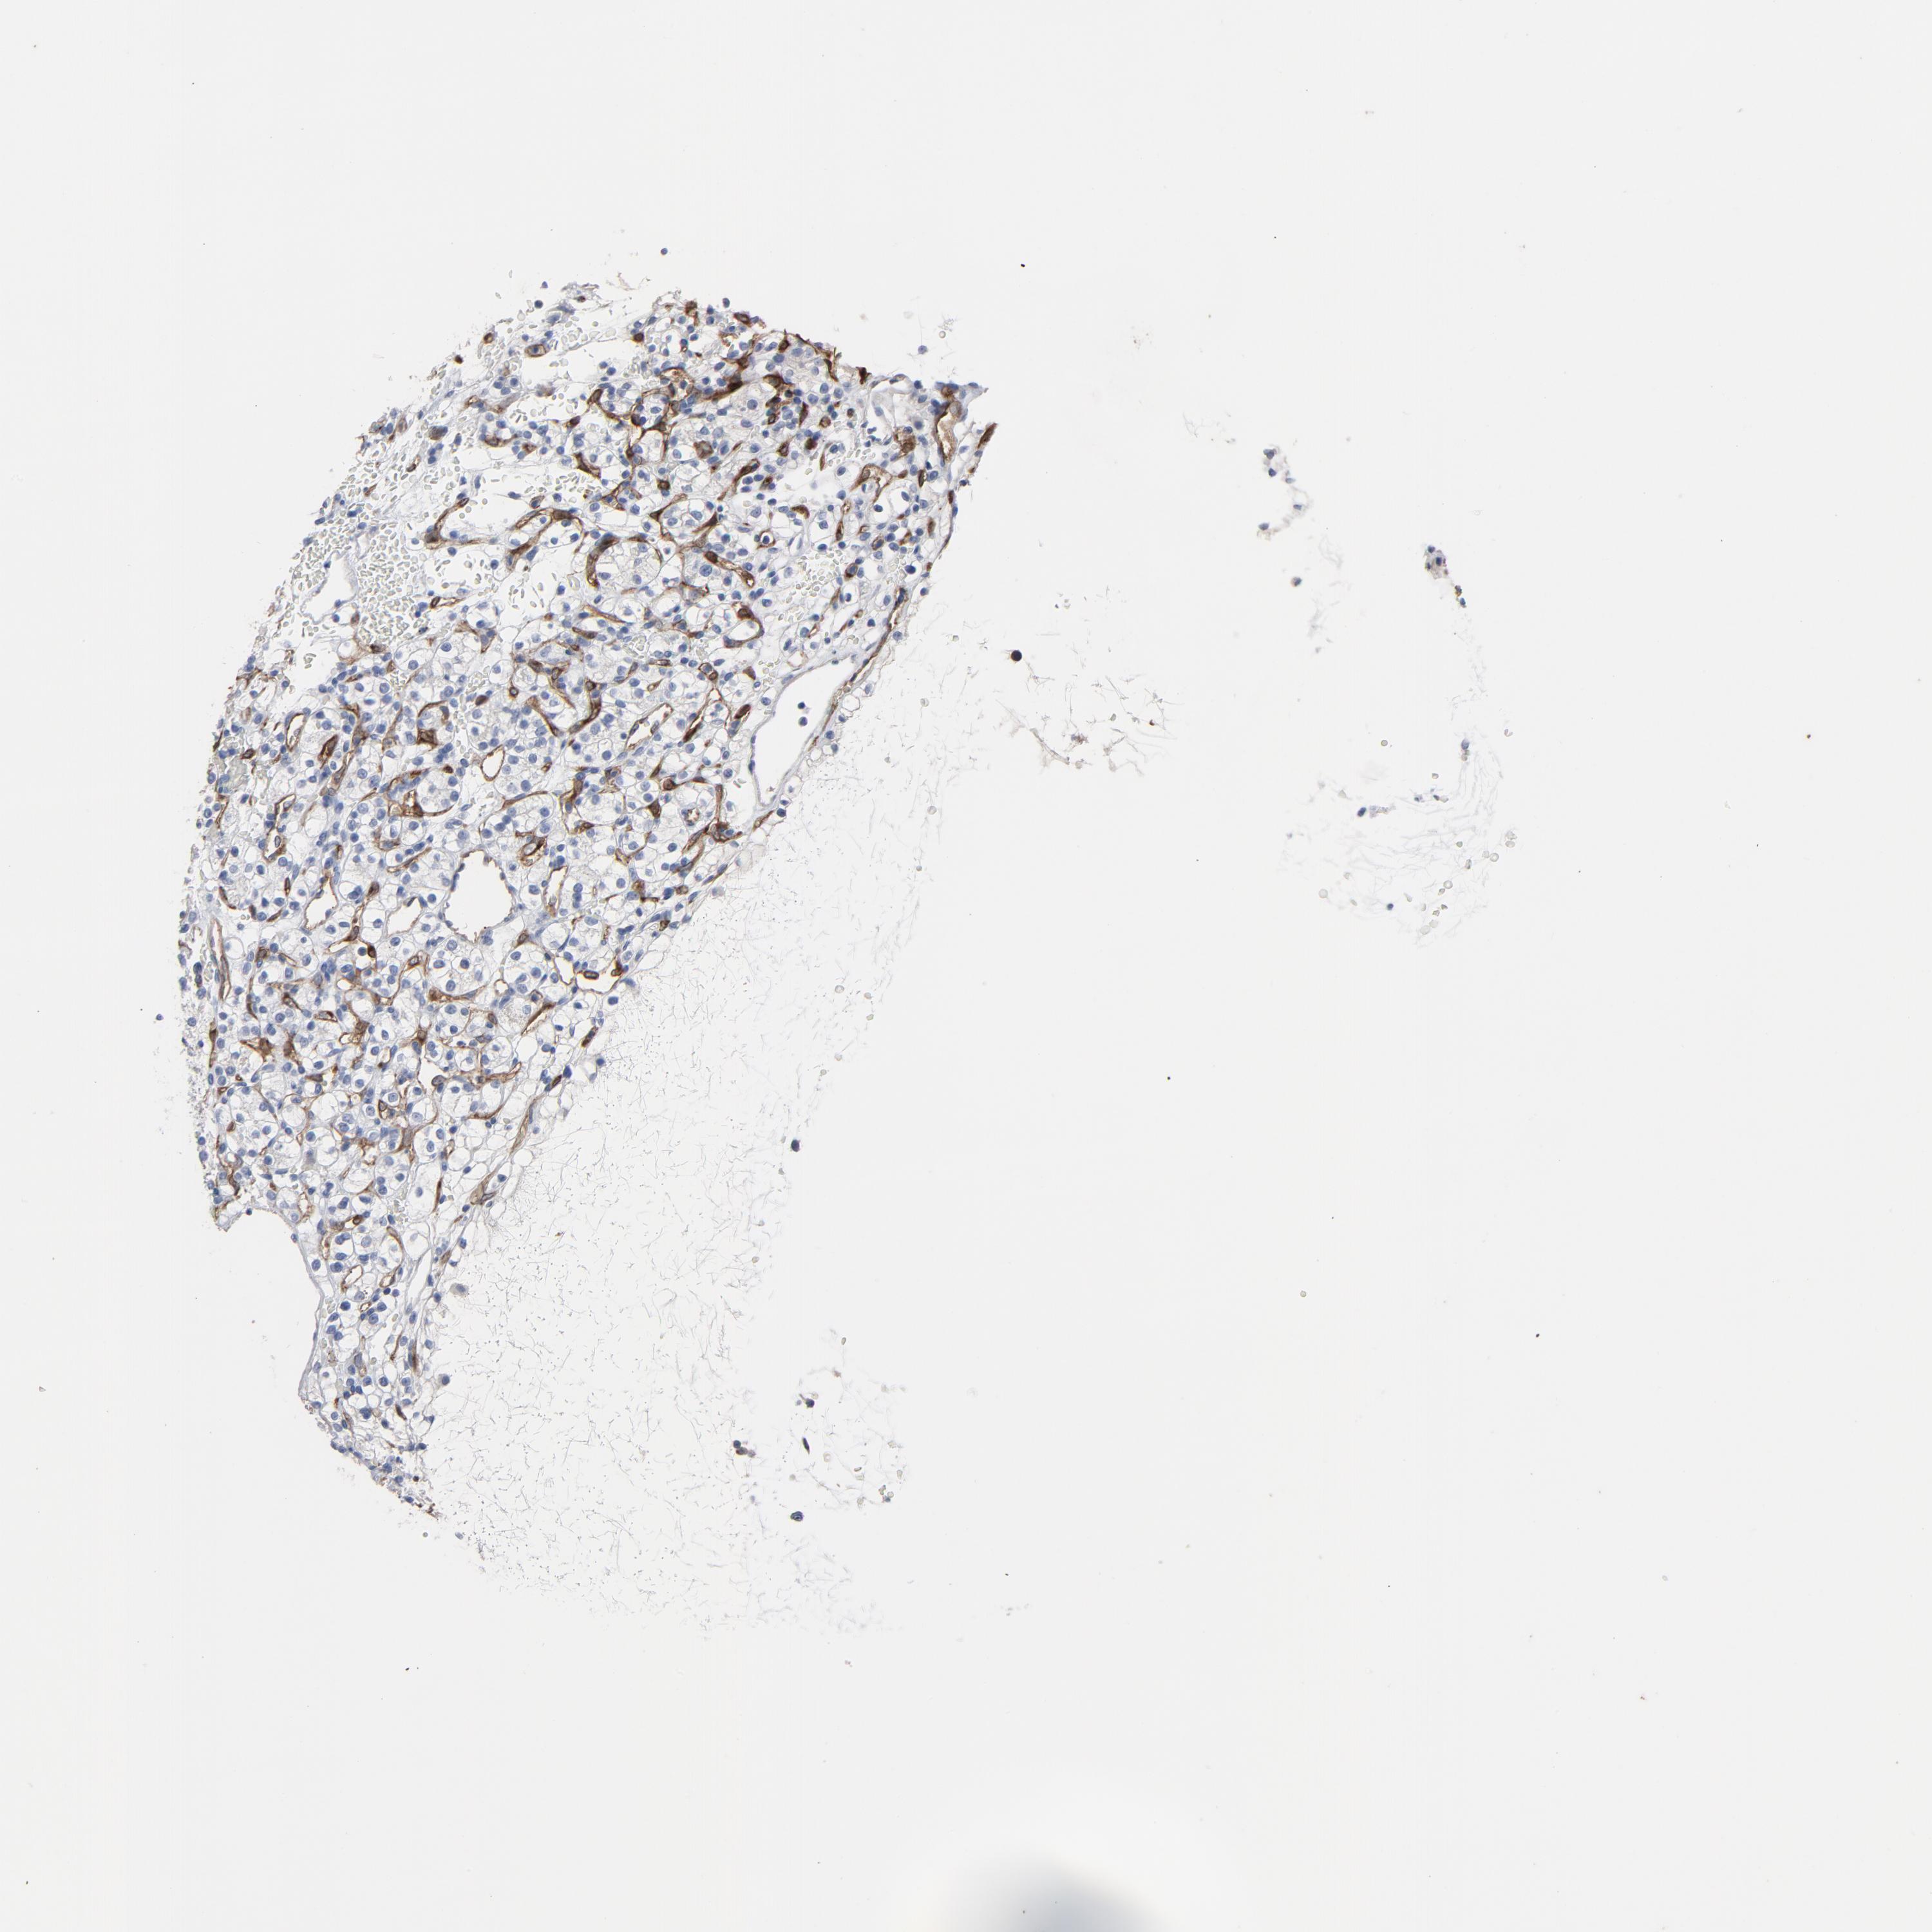

KIDNEY RENAL CLEAR CELL CARCINOMA (VALIDATION) - Interactive survival scatter ploti

The Survival Scatter plot shows the clinical status (i.e. dead or alive) for all individuals in the patient cohort, based on the same data that underlies the corresponding Kaplan-Meier plots. Patients that are alive at last time for follow-up are shown in blue and patients who have died during the study are shown in red.

The x-axis shows the expression levels (FPKM) of the investigated gene in the tumor tissue at the time of diagnosis. The y-axis shows the follow-up time after diagnosis (years). Both axes are complimented with kernel density curves demonstrating the data density over the axes. The top density plot shows the expression levels (FPKM) distribution among dead (red) and alive patients (blue). The right density plot shows the data density of the survived years of dead patients with high and low expression levels respectively, stratified using the cutoff indicated by the vertical dashed line through the Survival Scatter plot. This cutoff is automatically defined based on the FPKM cutoff that minimizes the p-score. The cutoff can be changed by dragging the vertical line or by entering a cutoff value in the square labeled "Current cut-off".

Under the Survival Scatter plot the p-score landscape (black curve; left axis) is shown together with dead median separation (red curve; right axis). Dead median separation is the difference in median mRNA expression between patients who have died with high and low expression, respectively. It is calculated as follows: median FPKM expression of dead patients with high expression - median FPKM expression of dead patients with low expression. This is intended to aid the user in visually exploring custom cutoffs and the associated p-scores and dead median separation.

Individual patient data is displayed and can be filtered by clicking on one or more of the category buttons on the top of the page. Categories describing expression level and patient information include: high, low, alive, dead, female, male and tumor stages. The scale of the x-axis can be toggled between linear and log-scale by clicking on the "x log" button. Mouse-over function shows TCGA ID, patient information and mRNA expression (FPKM) for each patient.

& Survival analysisi

Kaplan-Meier plots summarize results from analysis of correlation between mRNA expression level and patient survival. Patients were divided based on level of expression into one of the two groups "low" (under cut off) or "high" (over cut off). X-axis shows time for survival (years) and y-axis shows the probability of survival, where 1.0 corresponds to 100 percent.

KDR is validated prognostic, high expression is favorable in Kidney Renal Clear Cell Carcinoma (validation)

: 43.44

Average pTPM 38.7

Number of samples 100